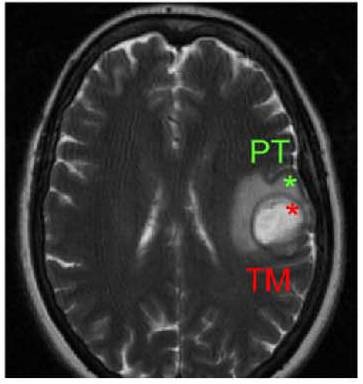

Cerebro afectado por un glioblastoma en el que se distingue la zona central de la masa tumoral (TM) de la zona periférica tumoral (PT). (Imagen: Atanasio Pandiella)